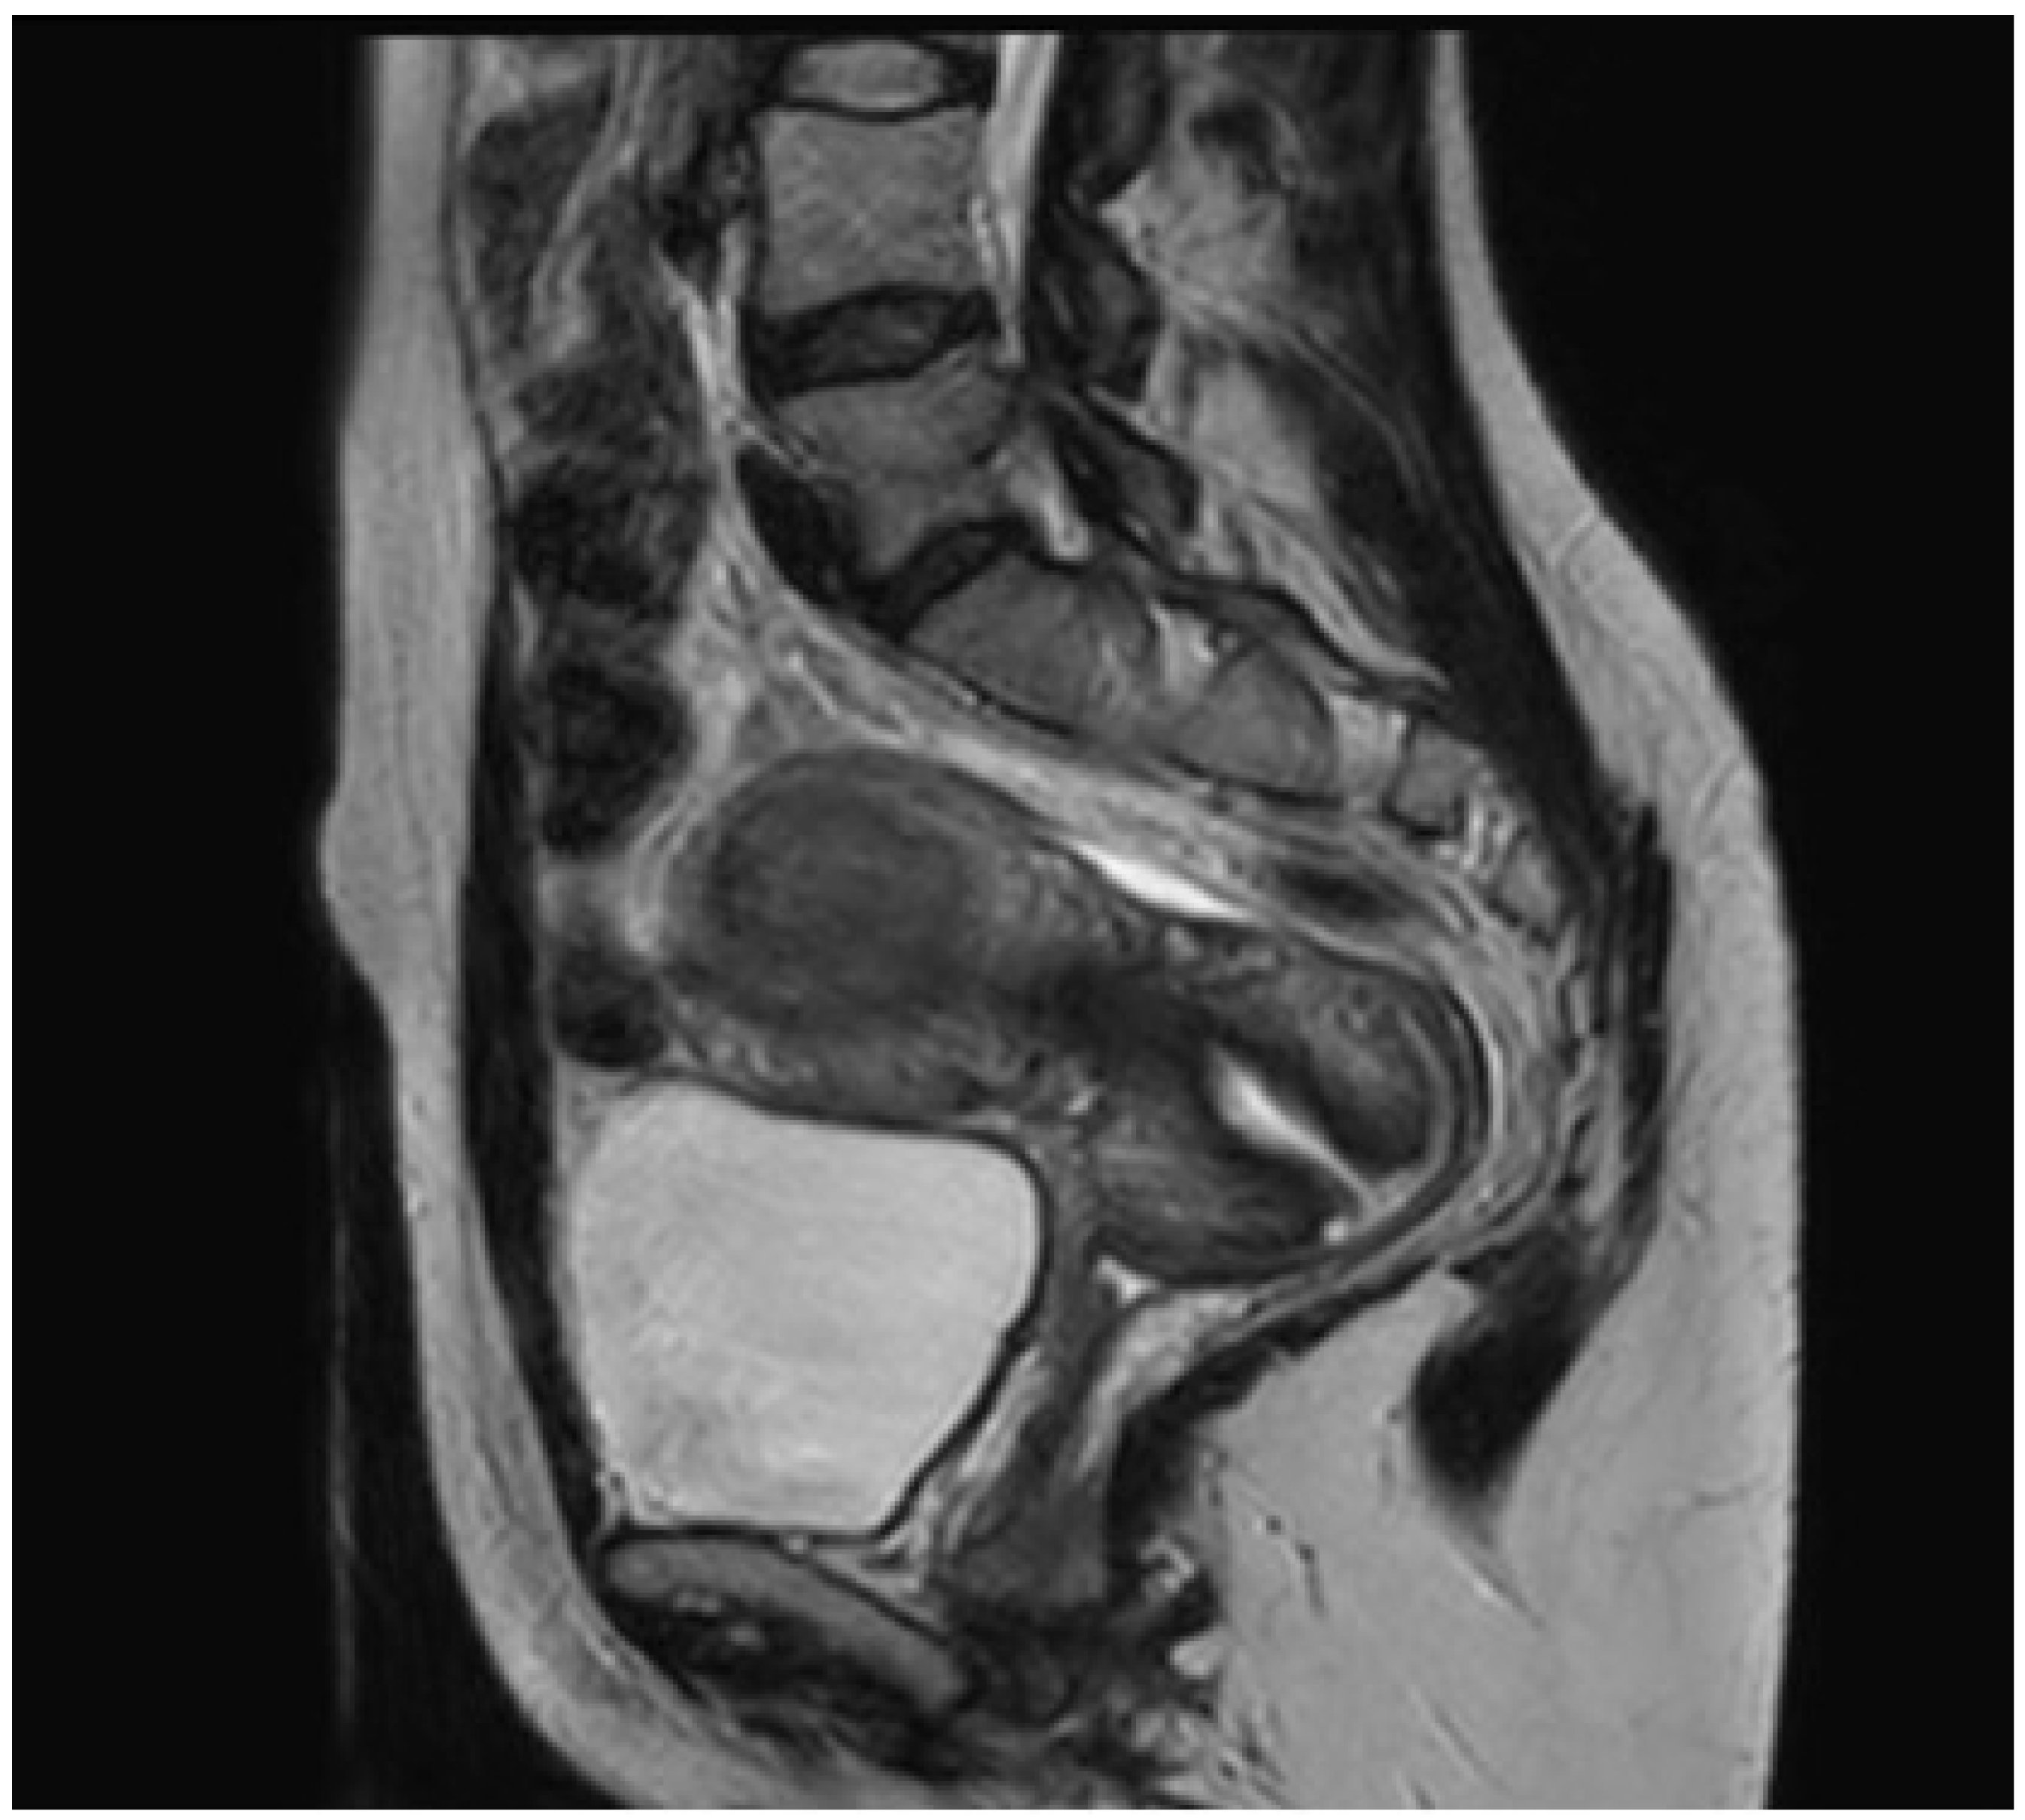

2.1. Case 1

2.2. Case 2